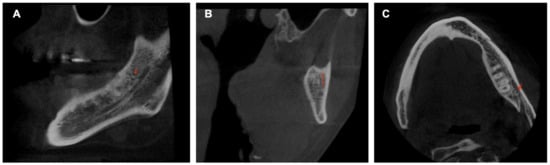

The MC was traced in the sagittal section, which made it possible to see its trajectory. First, the entry of the IAN to the MC in the MF was identified in the coronal section, setting the first reference point here. The following points were placed equidistant from each other following the course of the MC. The last point was fixed on the MF, taking the curve of the AL into account (Figure 1). It was ensured that each point was well located on all CBCT sections. The length of the MC was provided by the software after tracing the MC, and the records were taken in mm.

Figure 1. Sagittal slice CBCT image showing the tracing of the mandibular canal. The first reference point is located in the mandibular foramen, and the seventh reference point is in the mental foramen.